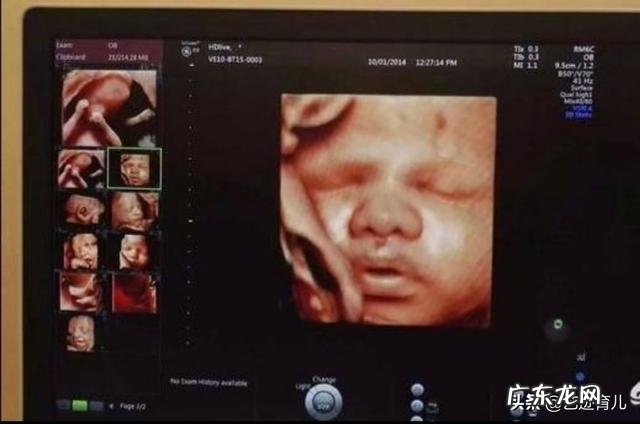

四维产检在多少周时去做最好?四维彩超是孕期最重要的检查,有些孕妇因为不注重产检,或者是预约时间过晚,导致错过做四维的最佳时机 。孕20-24周做四维彩超,效果是最好的 。

为什么四维彩超20-24周做最好?1.羊水量充足 。孕20-24周的时候,羊水量比较充足,方便胎儿在孕妇子宫内活动,医生也容易操作 。

2.胎儿大小合适 。孕20-24周的胎儿不大,四维彩超医生能看到胎儿的全身,十分清楚 。如果超过孕24周,胎儿越大,那么医生只能单个部位检查,有些部位因为胎儿继续发育,而无法再做检查 。

四维彩超可以排查胎儿面部,四肢,身体,泌尿和消化等系统的部分疾病,孕妇孕期一定要做四维 。